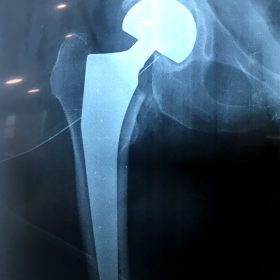

Σε αυτό το σημείο η Αρθροπλαστική Ισχίου αποτελεί μονόδρομο.

Παραδοσιακά οι αρθροπλαστικές ισχίου αποτελούνται από μια μεταλλική μπάλα – σφαίρα τοποθετημένη σε μια πλαστική κοιλότητα (κοτυλιαία πρόθεση).

Η πλαστική επιφάνεια στήριξης φθείρεται με την πάροδο του χρόνο, με ρυθμό μάλλον σχετιζόμενο με το επίπεδο δραστηριότητας του ατόμου. Αυτό έχει σαν επακόλουθο νεότεροι ασθενείς με μεγαλύτερο προσδόκιμο ζωής να έχουν αυξημένο ρίσκο αναγκαιότητας δεύτερης αρθροπλαστικής ισχίου (αναθεώρησης – Revision) επέμβαση που είναι πολυπλοκότερη και υπόκεινται σε υψηλότερο κίνδυνο επιπλοκών. Βάση των ανωτέρω, ιστορικά, η αρθροπλαστική ισχίου σπανίως εφαρμοζόταν σε ασθενείς κάτω των 60 ετών.

Χάρη στα νέα τεχνολογικά επιτεύγματα έχουν παραχθεί επιφάνειες στήριξης που ανταποκρίνονται σε μεγαλύτερα επίπεδα δραστηριότητας και αναμένεται να έχουν μεγαλύτερη διάρκεια ζωής. Αυτές οι καινούριες επιφάνειες στήριξης είναι συνήθως μέταλλο πάνω σε ειδικό σκληρότερο πλαστικό ή κεραμικό πάνω σε κεραμικό. Ως εκ τούτου, είναι τώρα πολύ πιο σύνηθες, νεότεροι ασθενείς να χειρουργούνται καθώς η πλειονότητα αυτών, που η αρθρίτιδα τους προκαλεί αφόρητους πόνους, επιλέγουν να έχουν ποιότητα ζωής από το να ζουν με τον πόνο.

Η αρθροπλαστική ισχίου αποτελεί μια αποτελεσματική επέμβαση αποκατάστασης και πρέπει να εφαρμόζεται μόνο όταν οι ασθενείς δεν είναι σε θέση να αντέξουν άλλο τον πόνο και την ανικανότητα και εφόσον τα πλεονεκτήματα καθώς και οι πιθανοί κίνδυνοι της μεθόδου έχουν εξηγηθεί πλήρως από το χειρουργό και έχουν κατανοηθεί από τον ασθενή.